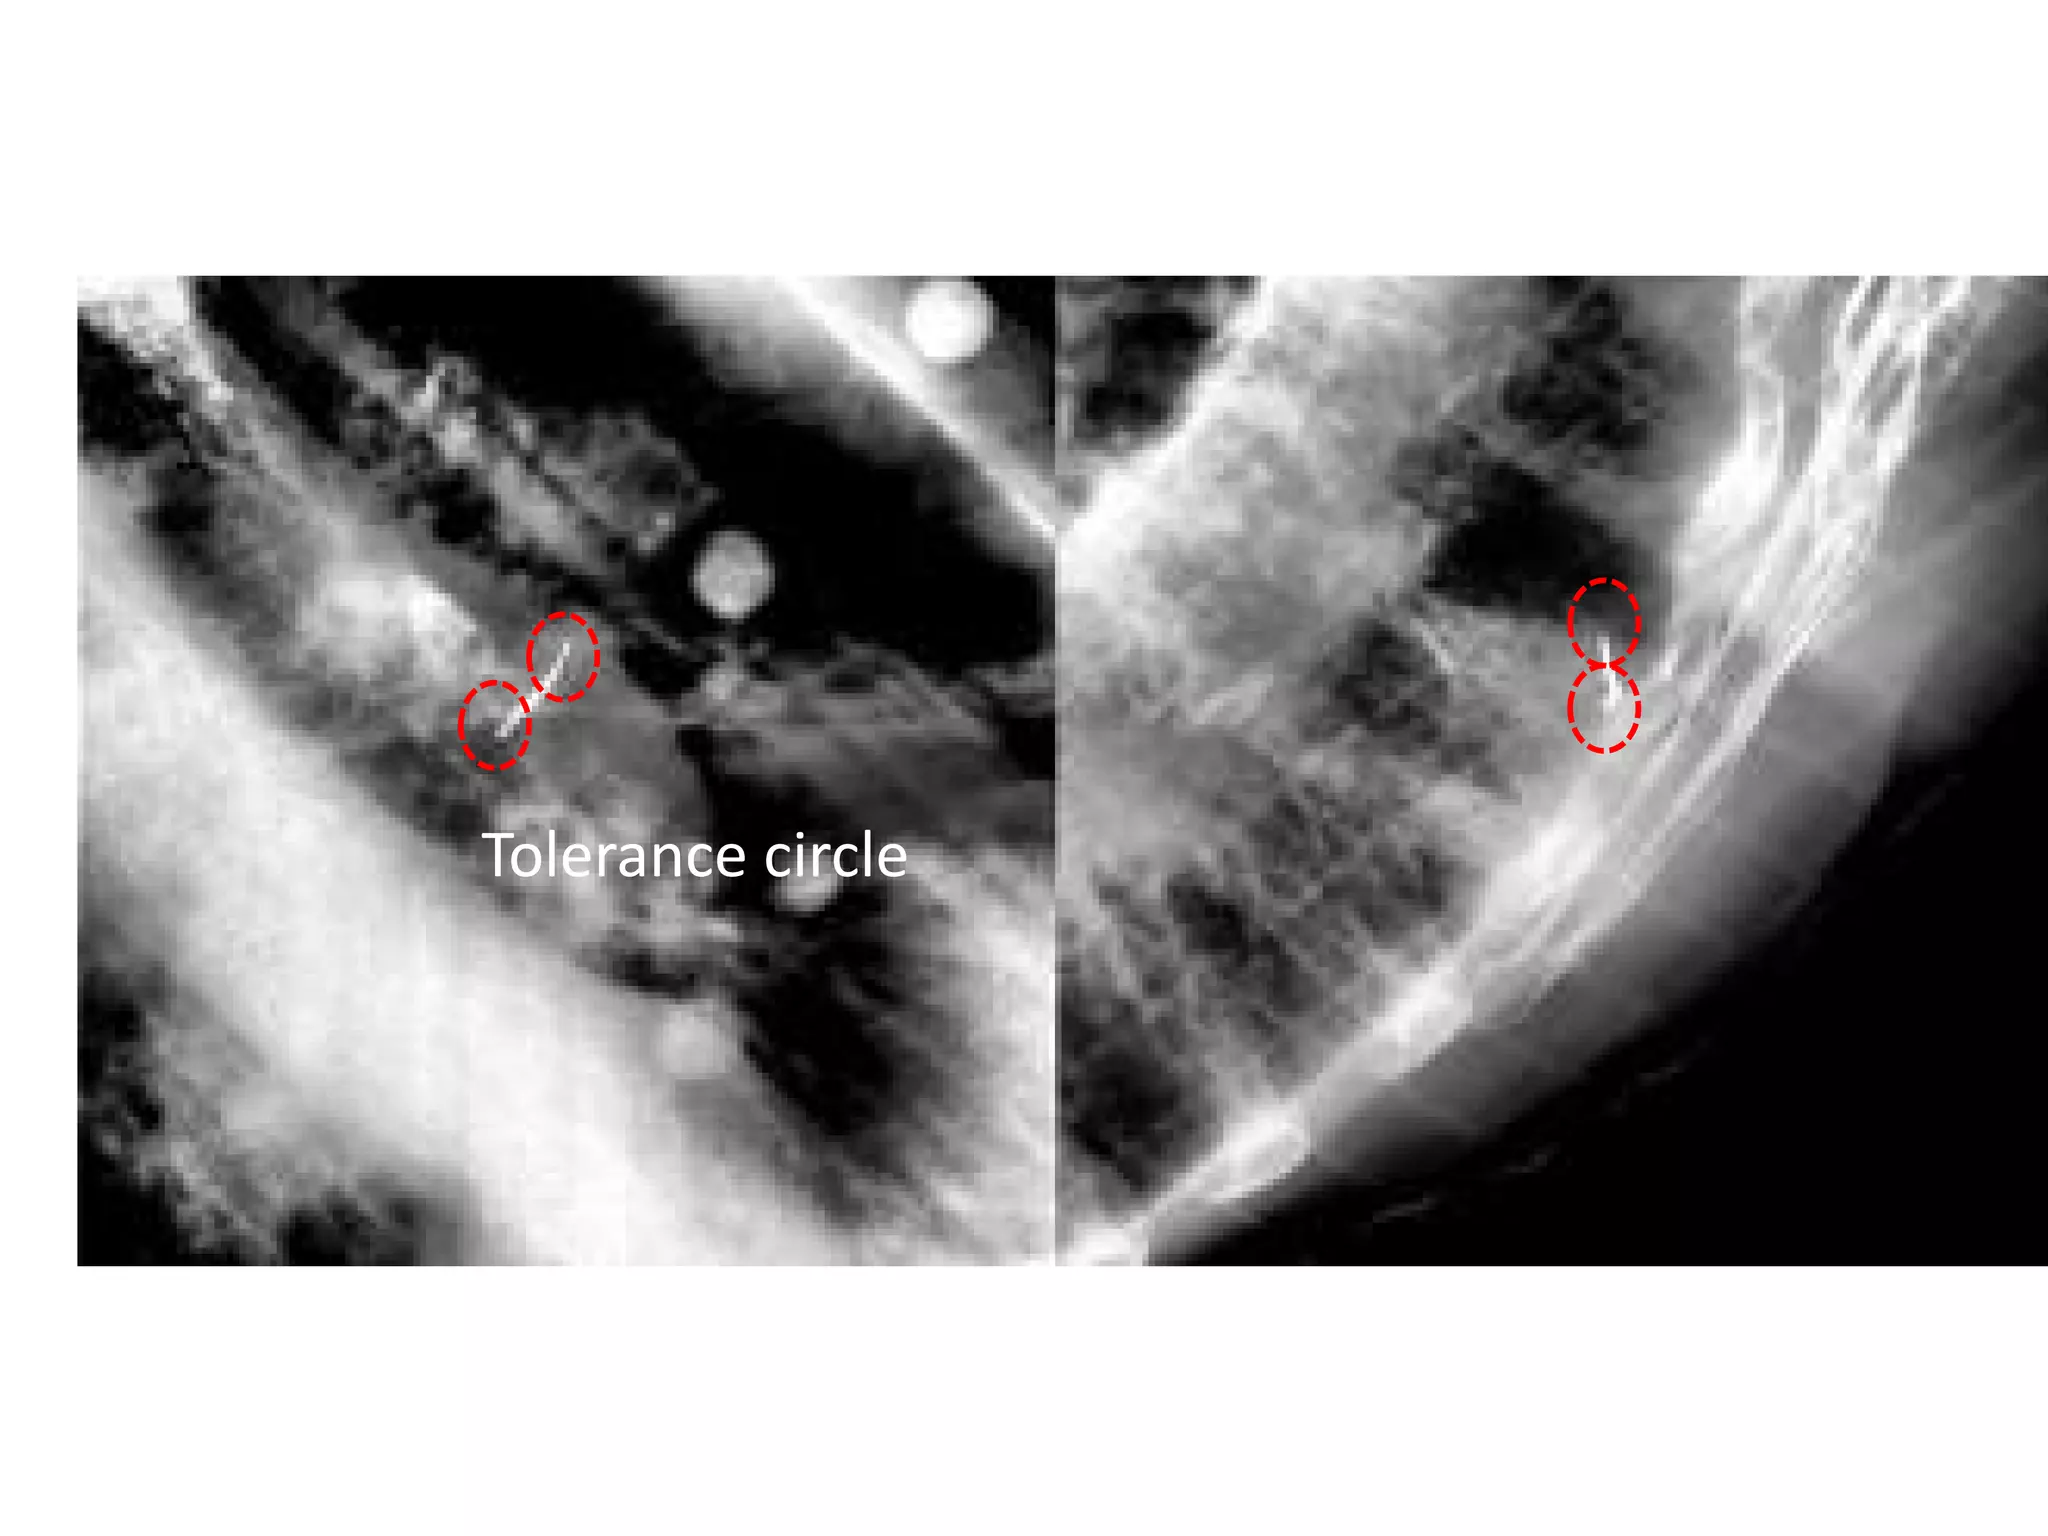

• Oblique image pairs are taken by ExacTrac

system’s stereoscopic X ray imagers.

• Internal fiducial ends are identified to the system

• The system builds a correlation model between

the end-positions and the respiratory phase

(accuracy of correlation 3mm).

• The treatment beam is then turned on and is

configured to treat ONLY in the gating window.

Tolerance circle